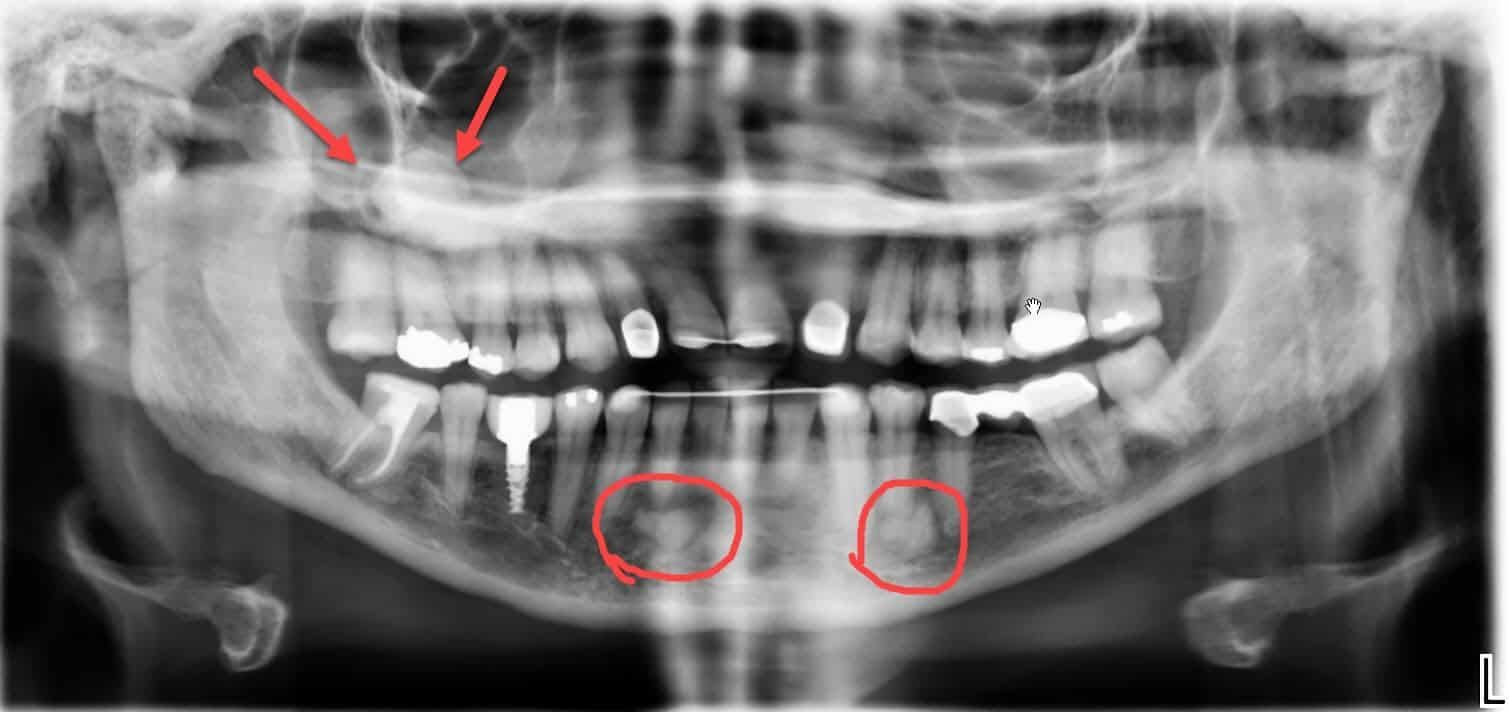

Panoramic Dental X-rays

The dental x-rays you see below are called panoramic x-rays. This kind is usually taken ever 3-5 years to screen for possible bone cysts, tumors, sinus abnormalities, etc. It’s also used to check growth and development in children, to make sure their teeth are developing normally. The first one shown here, which I labeled, is of a healthy patient.

But this panoramic x-ray, taken in the fall of 2019, surprised me with several unusual areas. There’s a large, dense, circular something in the right sinus, which definitely doesn’t belong there. There are also 2 irregular areas of unusually dense bone on the lower jaw. We have sent this patient to an oral surgeon for further evaluation.

Because we wanted more information about those unusual areas, we took another kind of dental x-ray, described next.